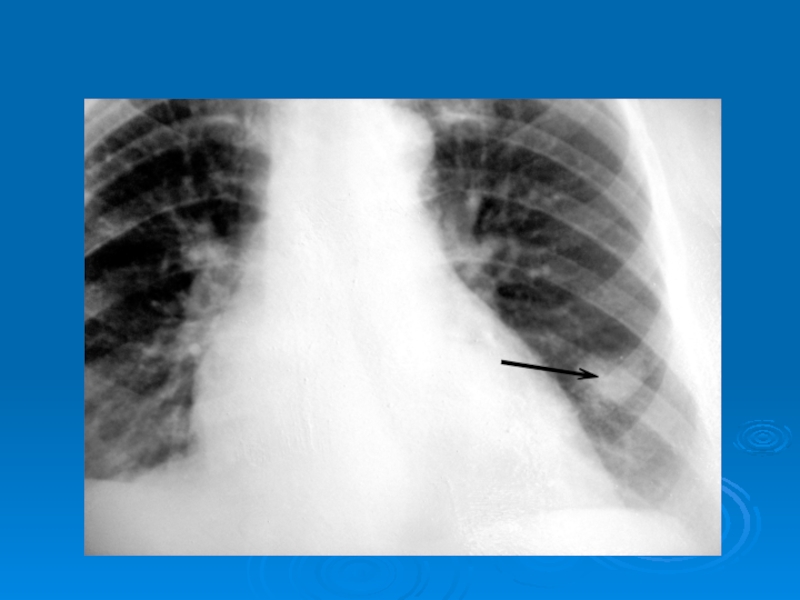

Слайд 39Затемнение части легочного поля (гидроторакс)

Затемнение части легочного поля (гидроторакс)